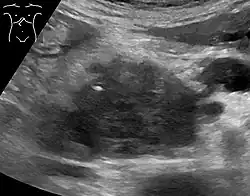

Medical imaging techniques, such as computed tomography (CT scan) and endoscopic ultrasound (EUS) are used both to confirm the diagnosis and to help decide whether the tumor can be surgically removed (its "resectability").[12] On contrast CT scan, pancreatic cancer typically shows a gradually increasing radiocontrast uptake, rather than a fast washout as seen in a normal pancreas or a delayed washout as seen in chronic pancreatitis.[66] Magnetic resonance imaging and positron emission tomography may also be used,[2] and magnetic resonance cholangiopancreatography may be useful in some cases.[40] Abdominal ultrasound is less sensitive and will miss small tumors, but can identify cancers that have spread to the liver and build-up of fluid in the peritoneal cavity (ascites).[12] It may be used for a quick and cheap first examination before other techniques.[67]

.jpg)